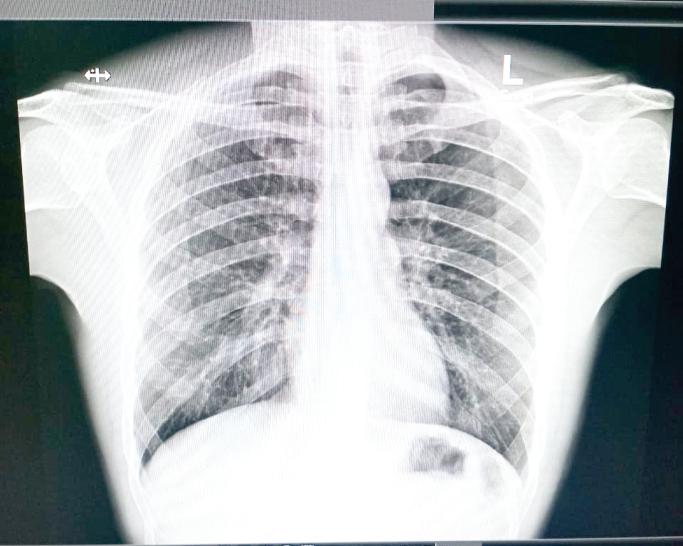

In an interview with this publication on Wednesday, Johnson detailed the attack and provided images of the X-Rays done, as well as videos of him at the Georgetown Public Hospital Corporation(GPHC).

The X-Ray image showing the pooled blood on the left side of his chest.